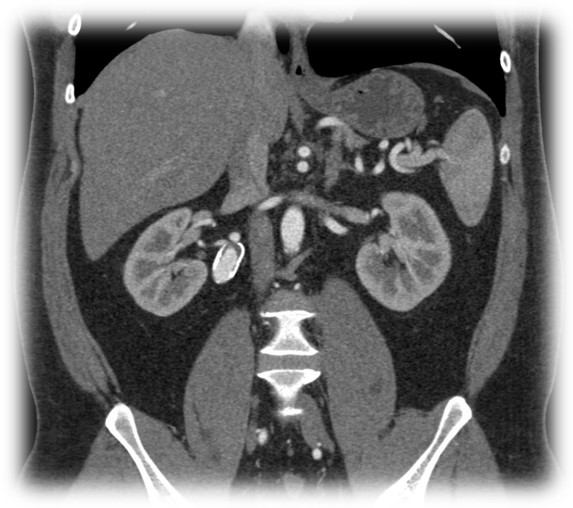

Pár kép az oktatás radiológiai részéről:

(SE-OKK, SIEMENS, CTISUS)